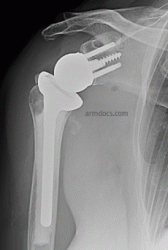

After surgery

A Reverse shoulder replacement is performed under a combination of general and regional anaesthesia. The shoulder is exposed, the humeral head (ball fragment) is removed, a metal hemisphere is fixed on to the socket (glenoid) of the shoulder and a metal prosthesis with a plastic cup insert is implanted in the shaft of the humerus. The tuberosities (bone fragments which carry tendon attachments) are realigned and then fixed to the prosthesis and humeral shaft with sutures or cable. The fixation is supplemented with bone graft using bone from the removed fragment.